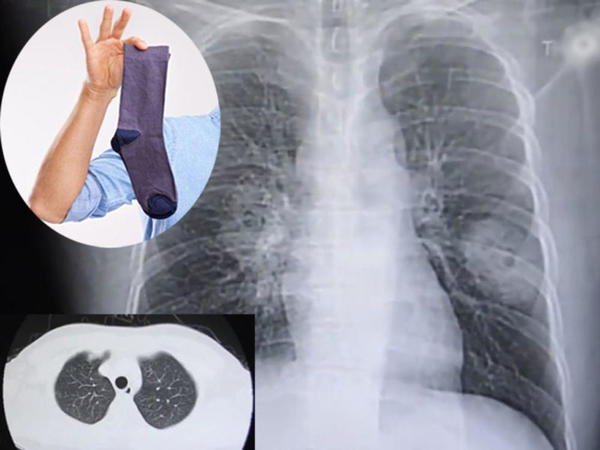

从莆田来漳州务工的38岁彭某,怎么也没有想到,自己的一个不良嗜好,居然导致了肺部真菌感染。12月初,彭某因咳嗽、胸闷一周,住进了漳州第909医院(原第175医院)呼吸结核科。通过详细询问病情,他的一个小癖好引起了医务人员的注意。原来,彭某下班后经常喜欢拿自己的臭袜子闻一闻,他说“就像上了瘾一样”。

经肺穿刺病理检测,彭某最终被诊断为真菌病。采取了对症治疗后,目前患者恢复情况良好。

呼吸结核科主治医师麦转英介绍,肺真菌病是指真菌引起的支气管肺部真菌感染。通常肺真菌病患者具有一种或多种基础疾病,老龄、机体免疫力严重下降也容易受到真菌感染。她推测,彭某之所以患病,可能跟他发病前熬夜照顾幼小的孩子、机体免疫力下降有关系。

麦转英提醒,虽然我们正常人体口腔中有真菌寄生,卫生间、土壤中也都有真菌存在,但在临床实际中,肺真菌病在呼吸道感染性疾病中并不多发,主要还是跟免疫情况有关。一旦吸入真菌量大,超过了人的机体防御功能时就可能发病。